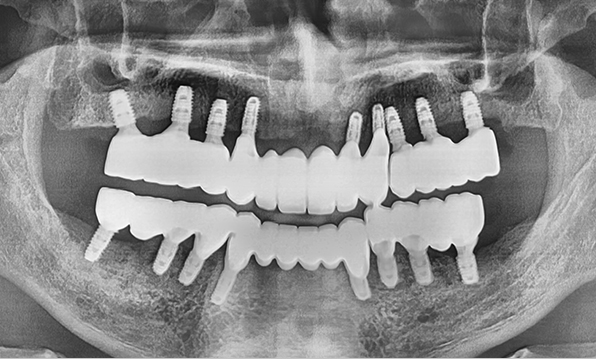

Full Placement

Using a method of placing 8–9 implants in the maxilla and 8 implants in the mandible, this approach fully restores all 28 natural teeth, creating an oral environment most closely resembling

natural dentition.

Before After